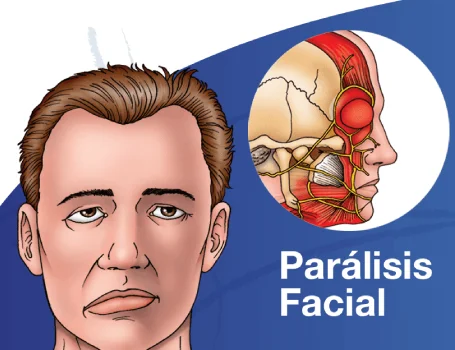

Entendiendo la Parálisis Facial: Una Perspectiva Neuroquirúrgica

¿Qué es la parálisis facial?En esencia, la parálisis facial se refiere a la debilidad...